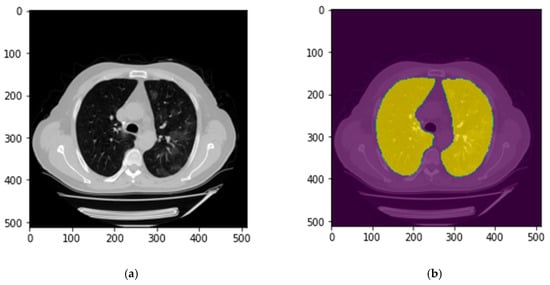

2.4. Image Postprocessing and Correction